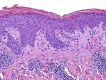

PP: histopathologic examination of skin lesions of patient 1. Parakeratosis, acanthosis, few dyskeratotic cells, mild vacuolar change at the dermoepidermal junction, and superficial perivascular lymphocytic infiltrate.